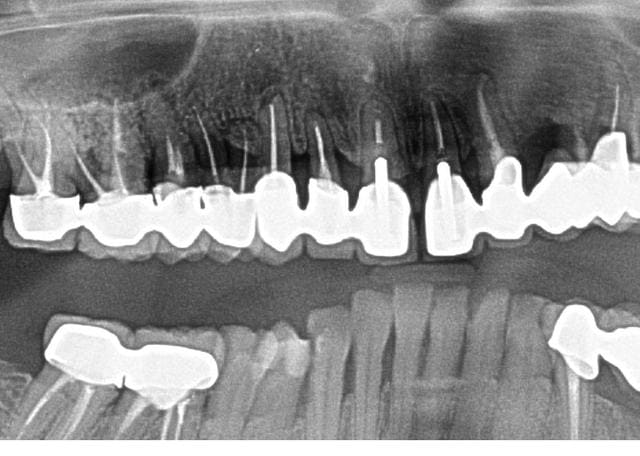

Exemple de ROG limite . En fait, je pensais avoir mis du bio os, mais meme pas : c'était du RTR cone.

intervention sur 12 13 14 en 2007. pano de controle en 2012.

14 est limite, a cause de la furcation, mais 12 est plutot pas mal. ( il y a eu resection sur 13, et 15 est pas terrible, mais c'est pas le sujet )